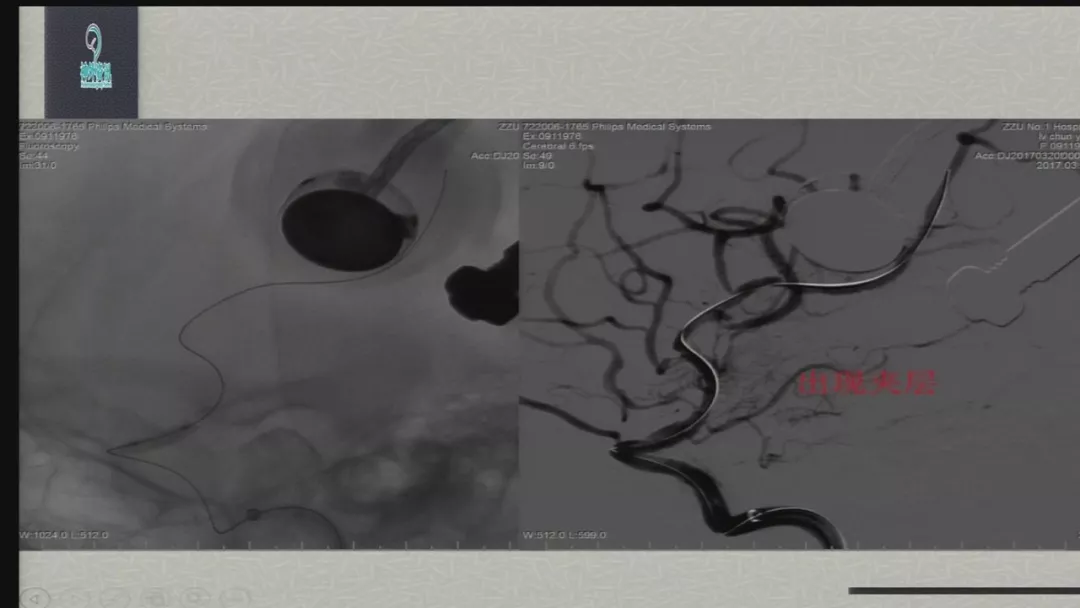

徐浩文:Neuroform EZ在ICAS治疗中的应用丨第七届全国介入医学工程大会精彩回顾

今天为大家分享的是由郑大一附院徐浩文教授在第七届全国介入医学工程大会上带来的“Neuroform EZ在ICAD治疗中的应用”精彩讲课视频和PPT,欢迎观看!(内容未经讲者审核,不当之处请与我们联系)